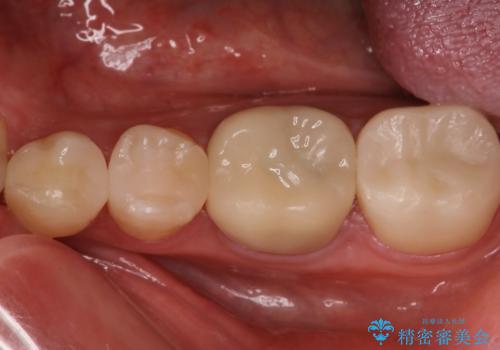

前歯のセラミック治療

担当医 青山卓弘